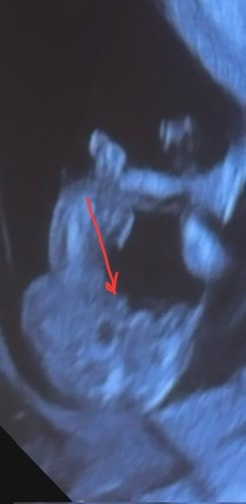

смотрим фото малыша

2 фото - закинул ножку на ножку, вид со стороны попы (снизу)

Что видите на 2 фото, мальчик, девочка? Я пока ничего, через 8 дней на НИПТ узнаю точно 100%

Кактусеныш, блин, я часами уже смотрю и думаю, это ведь не похоже не пенис? Потому что как будто похоже 😆😭

Mia, да нет) Скорее «пирожок» вижу

Но могу ошибиться. Но это точно не пенис))